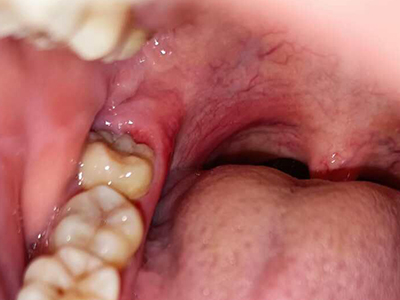

智齿冠周炎挨着嗓子的牙龈处溃烂发白图

智齿冠周炎患者磨牙后区萌出第三个磨牙周围牙龈组织肿痛甚至溃烂发白,多是由于阻生等原因导致其萌出不全,形成牙周袋,牙周袋内容易积存食物及细菌导致。